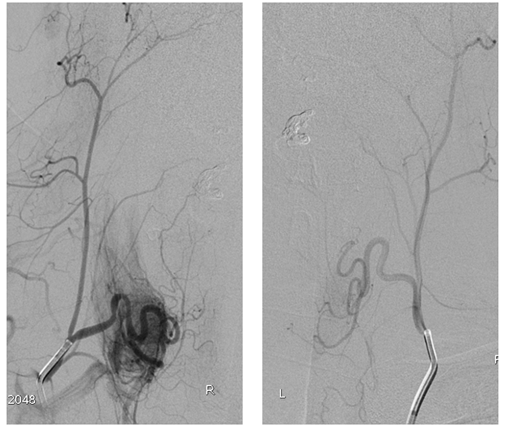

正侧位,甲状颈干造影静脉期,显示瘘口主要经颈髓前(箭头)、后静脉(黑箭)引流入颅,引流静脉迂曲、增粗、扩张,部分经椎旁静脉丛引流。动静脉之间未见明显畸形团结构。

左侧甲状颈干选择性造影,显示瘘口位置及扩张静脉与对侧形态形态相似。考虑双侧颈升动脉供应相同瘘口。予以ONXY进行栓塞瘘口,栓塞物控制于扩张的静脉球内。